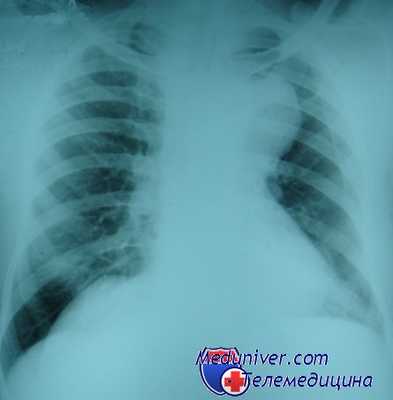

Несмотря на очень большие размеры, оно длительное время может протекать бессимптомно. Важно, что почти всегда мы можем наблюдать связь со щитовидной железой. Это образование располагается в области верхней апертуры. Может быть в переднем или заднем средостении. Как правило, оттесняет и суживает трахею, что на рентгеновских снимках создает очень характерную типичную картину.

Если вы посмотрите на обзорный снимок в прямой проекции, то сразу же будет видно, насколько изменилась конфигурация воздушного столба в трахее на уровне грудино-ключичных расчленений и выше в области верхней апертуры. Трахея оттеснена по дуге вправо и практически достигает контура средостения и несколько сужена.

Почему? Ответ на этот вопрос в компьютерно-томографическом исследовании. Два огромных узла, один из которых располагается на шее. Второй в переднем средостении. Оба гиперваскулярны, неоднородной структуры. Это типичная картина огромных размеров внутригрудного зоба, который занимает переднюю часть средостения.